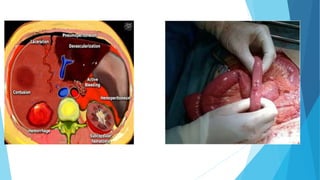

INTERACTIVE SESSION

 I WILL SHARE SOME CLINICAL PICTURES

 I WILL SELECT DIRECTLY WHO WILL ANSWER THE QUESTION

 YOU WILL HAVE ONE MINUTE TO THINK IN YOUR ANSWER.